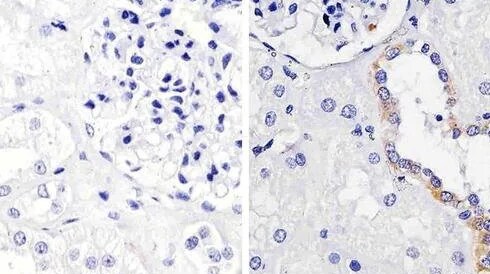

Antibodies

Avec plus de 400 000 anticorps primaires et secondaires provenant des fournisseurs les plus fiables et les plus innovateurs en sciences de la vie, le canal commercial Fisher Scientific offre la plus grande sélection de l’industrie pour les applications en sciences de la vie. Que vous effectuez une ELISA ou la cytométrie de flux, utilisez les méthodes de transfert western afin d’identifier votre cible de choix, ou multiplexez avec des anticorps conjugués fluorescents, vous trouverez le bon anticorps dans notre collection.